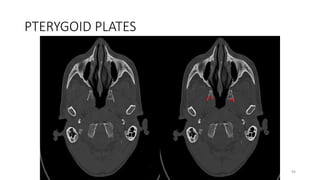

PTERYGOID PLATES